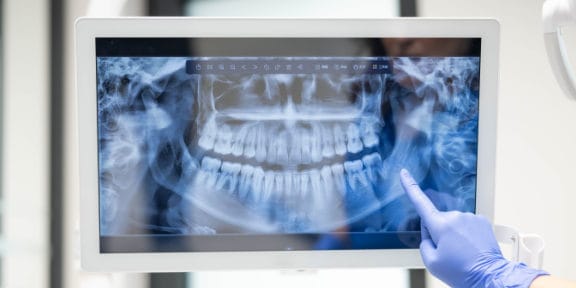

Digital Panoramic X-Rays

Panoramic x-rays offer patients a complete detailed image of the entire mouth including the teeth, jaw (upper and lower), sinuses, and TMJ.

It provides a complete picture on how everything looks and relates to each other.